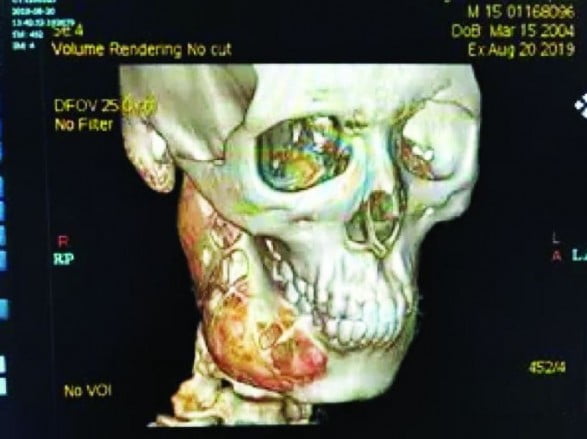

ومع تزايد حدّة الألم، وفقاً لما ذكر موقع “آسيا وان”، قرر أقرباء الشاب الذي لم يتم الكشف عن اسمه، أخذه للمستشفى، حيث أظهرت صور الأشعة المقطعية وجود ما يعرف بالورم الأرومي المينائي الذي كان يسبب ألم الأسنان، وهو ورم حميد أصاب فكه السفلي. إلا أن تلكؤ الشاب عن زيارة الطبيب أسفر عن ظهور عدة إصابات في العظام أبرزها حفرة كبيرة في عظمة الفك.

ويأمل أقرباء الشاب أن يتماثل للشفاء التام بعد أن أجريت له عملية جراحية لاستئصال الورم واستعادة شكل الفك المتضرر.